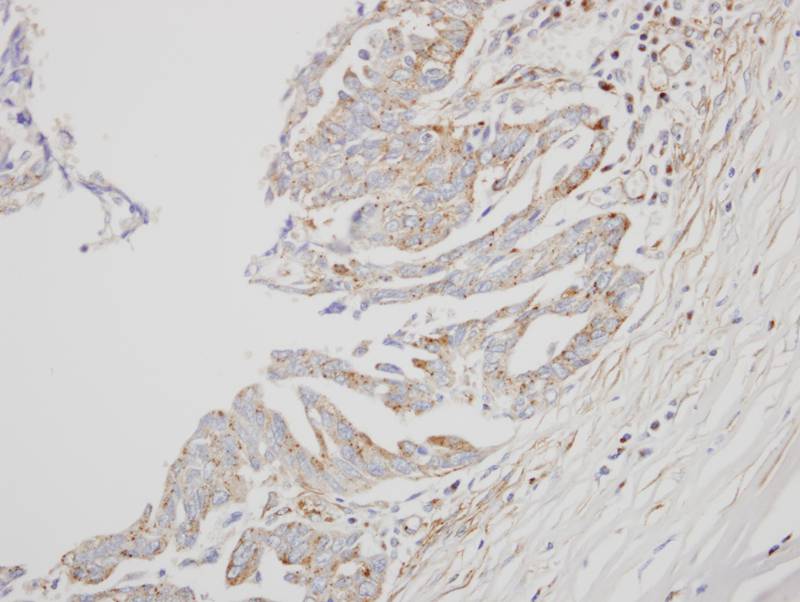

Immunohistochemical analysis of paraffin-embedded OVCA xenograft, using interferon alpha 8 antibody at 1: 500 dilution.